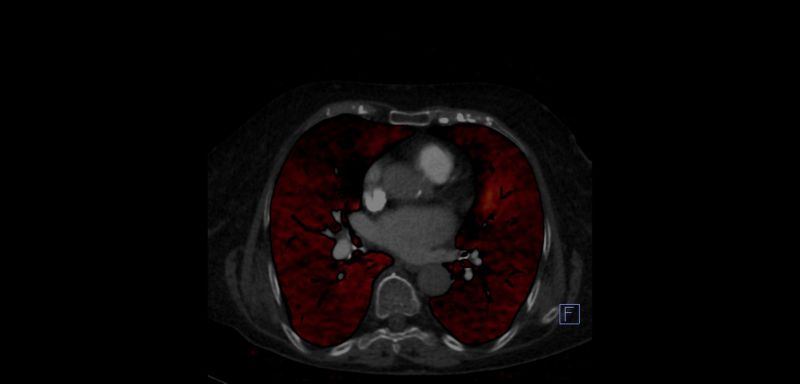

Sistemin bu özelliği sayesinde, Başkent Üniversitesi Adana Hastanesi bünyesindeki yeni versiyon Dual-Enerji bilgisayarlı tomografi cihazında da normalde diğer merkezlerde kullanılan kontrast maddenin yaklaşık 1/3 miktarı ile son derece başarılı Akciğer damar görüntülemesi (Pulmoner  Anjiografi) ve aynı seansta akciğerlerin kanlanma düzeyini gösteren “Perfüzyon” değerlendirmesi de yapılabilmektedir. Bu sayede merkezimizde, başta böbrek sorunu olan hastalar olmak üzere birçok hasta grubunun kontrast madde kaynaklı böbrek hasarı (nefrotoksisite) olmadan akciğer damar yatağı (Pulmoner  Anjiografi) görüntülemesi yapılabilmektedir.

OLGU 2.

Normal tomografide PTE demostre edilememiştir. Dual BT Perfüzyon BT ile Kronik Pulmoner Emboli'si olan olguda sağ orta lobta perfüzyon defekti gözlenmektedir.